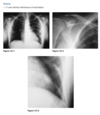

61yr old woman with shoulder pain

AP Radiograph of left shoulder in external and internal rotation (1 & 2) - globular foci of calcification in expected location of supraspinatus (White arrow) and infraspinatus (black arrow) and pectorals major

DIAGNOSIS: Hydroxyapatite deposition disease

(HADD)

HADD consists of crystal deposition in

and around joints, without a known cause.

AKA calcific tendonitis

On radiographs, the calcium deposits appear cloud-

like and amorphous and can involve the tendon,

ligament, bursa, or joint capsule. Intraarticular crys-

tal deposition can destroy the joint space, resulting

in a condition referred to as “Milwaukee shoulder.”

On CT,

­ accompanying erosion of the underlying bone can be

seen. CT appearance has been described as commonly

having a flame-shaped or comet-tail configuration of

the calcifications

If not in shoulder/region not common for HADD ?Malignancy